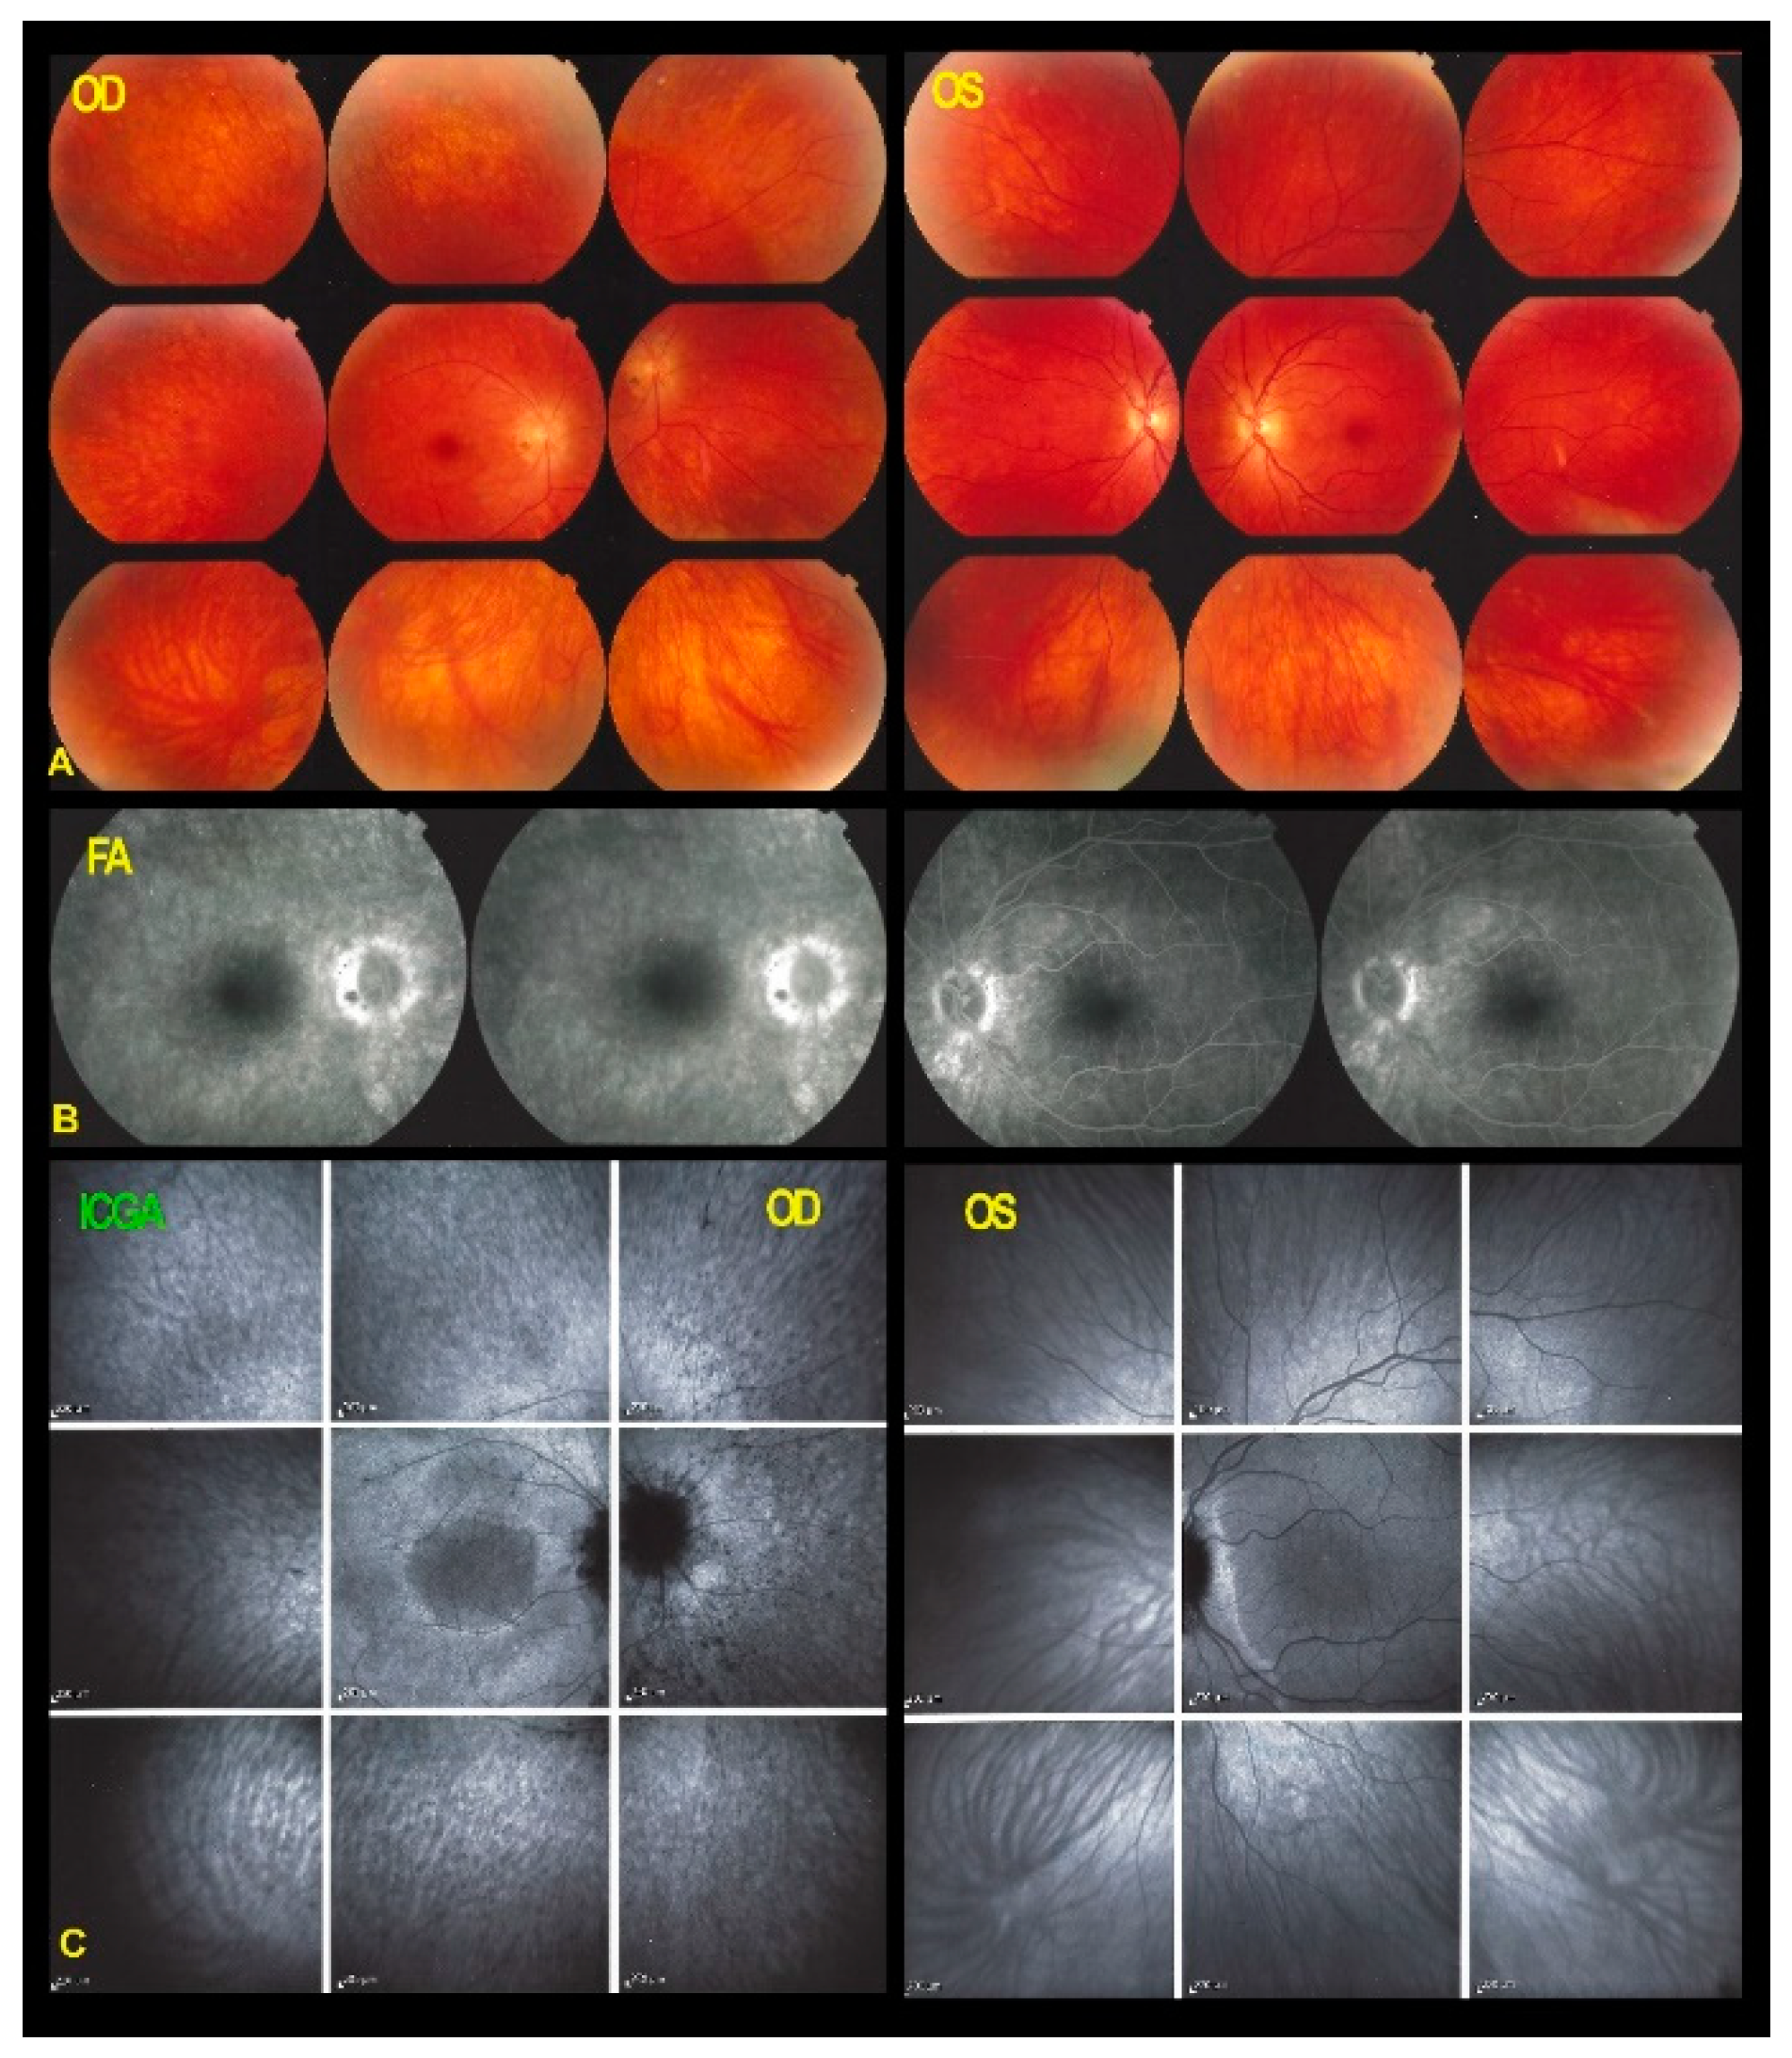

| BL-FAF | Hyperautofluorescence [increased exposure of RPE lipofuscin following loss of photoreceptor OS] |

| Hypoautofluorescence in severely affected areas [chorioretinal atrophy] | |

| ICGA | Preserved fluorescence [indicates integrity of choriocapillaris] |

| SD-OCT | Loss of photoreceptors outer segment in diseased areas |

| FA | Faint late hyperfluorescence in diseased areas [indicates loss of photopigment of photoreceptors OS] |

| Hyperfluorescent areas early and late [indicates chorioretinal atrophy-window effect)– | |

| Follow-Up | Areas of chorioretinal atrophy; secondary choriocapillaris involvement |